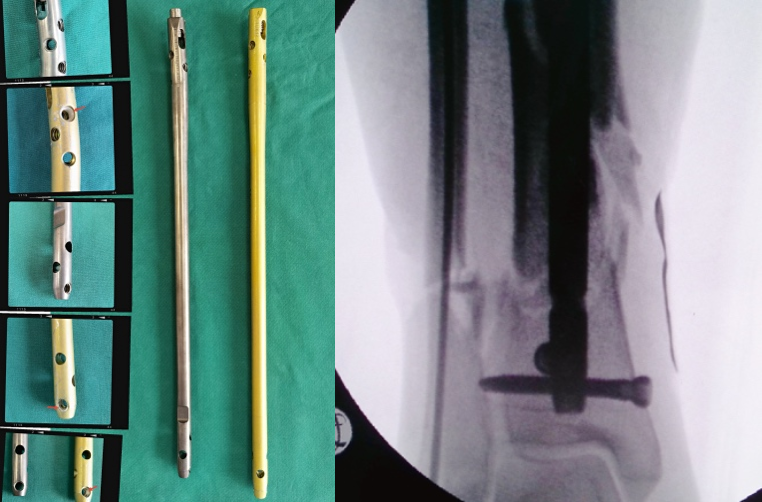

3、使用特殊的「 锁定型髓内钉 」远端即便只锁 2 枚锁钉依然稳定。

腓骨采用弹性髓内钉固定